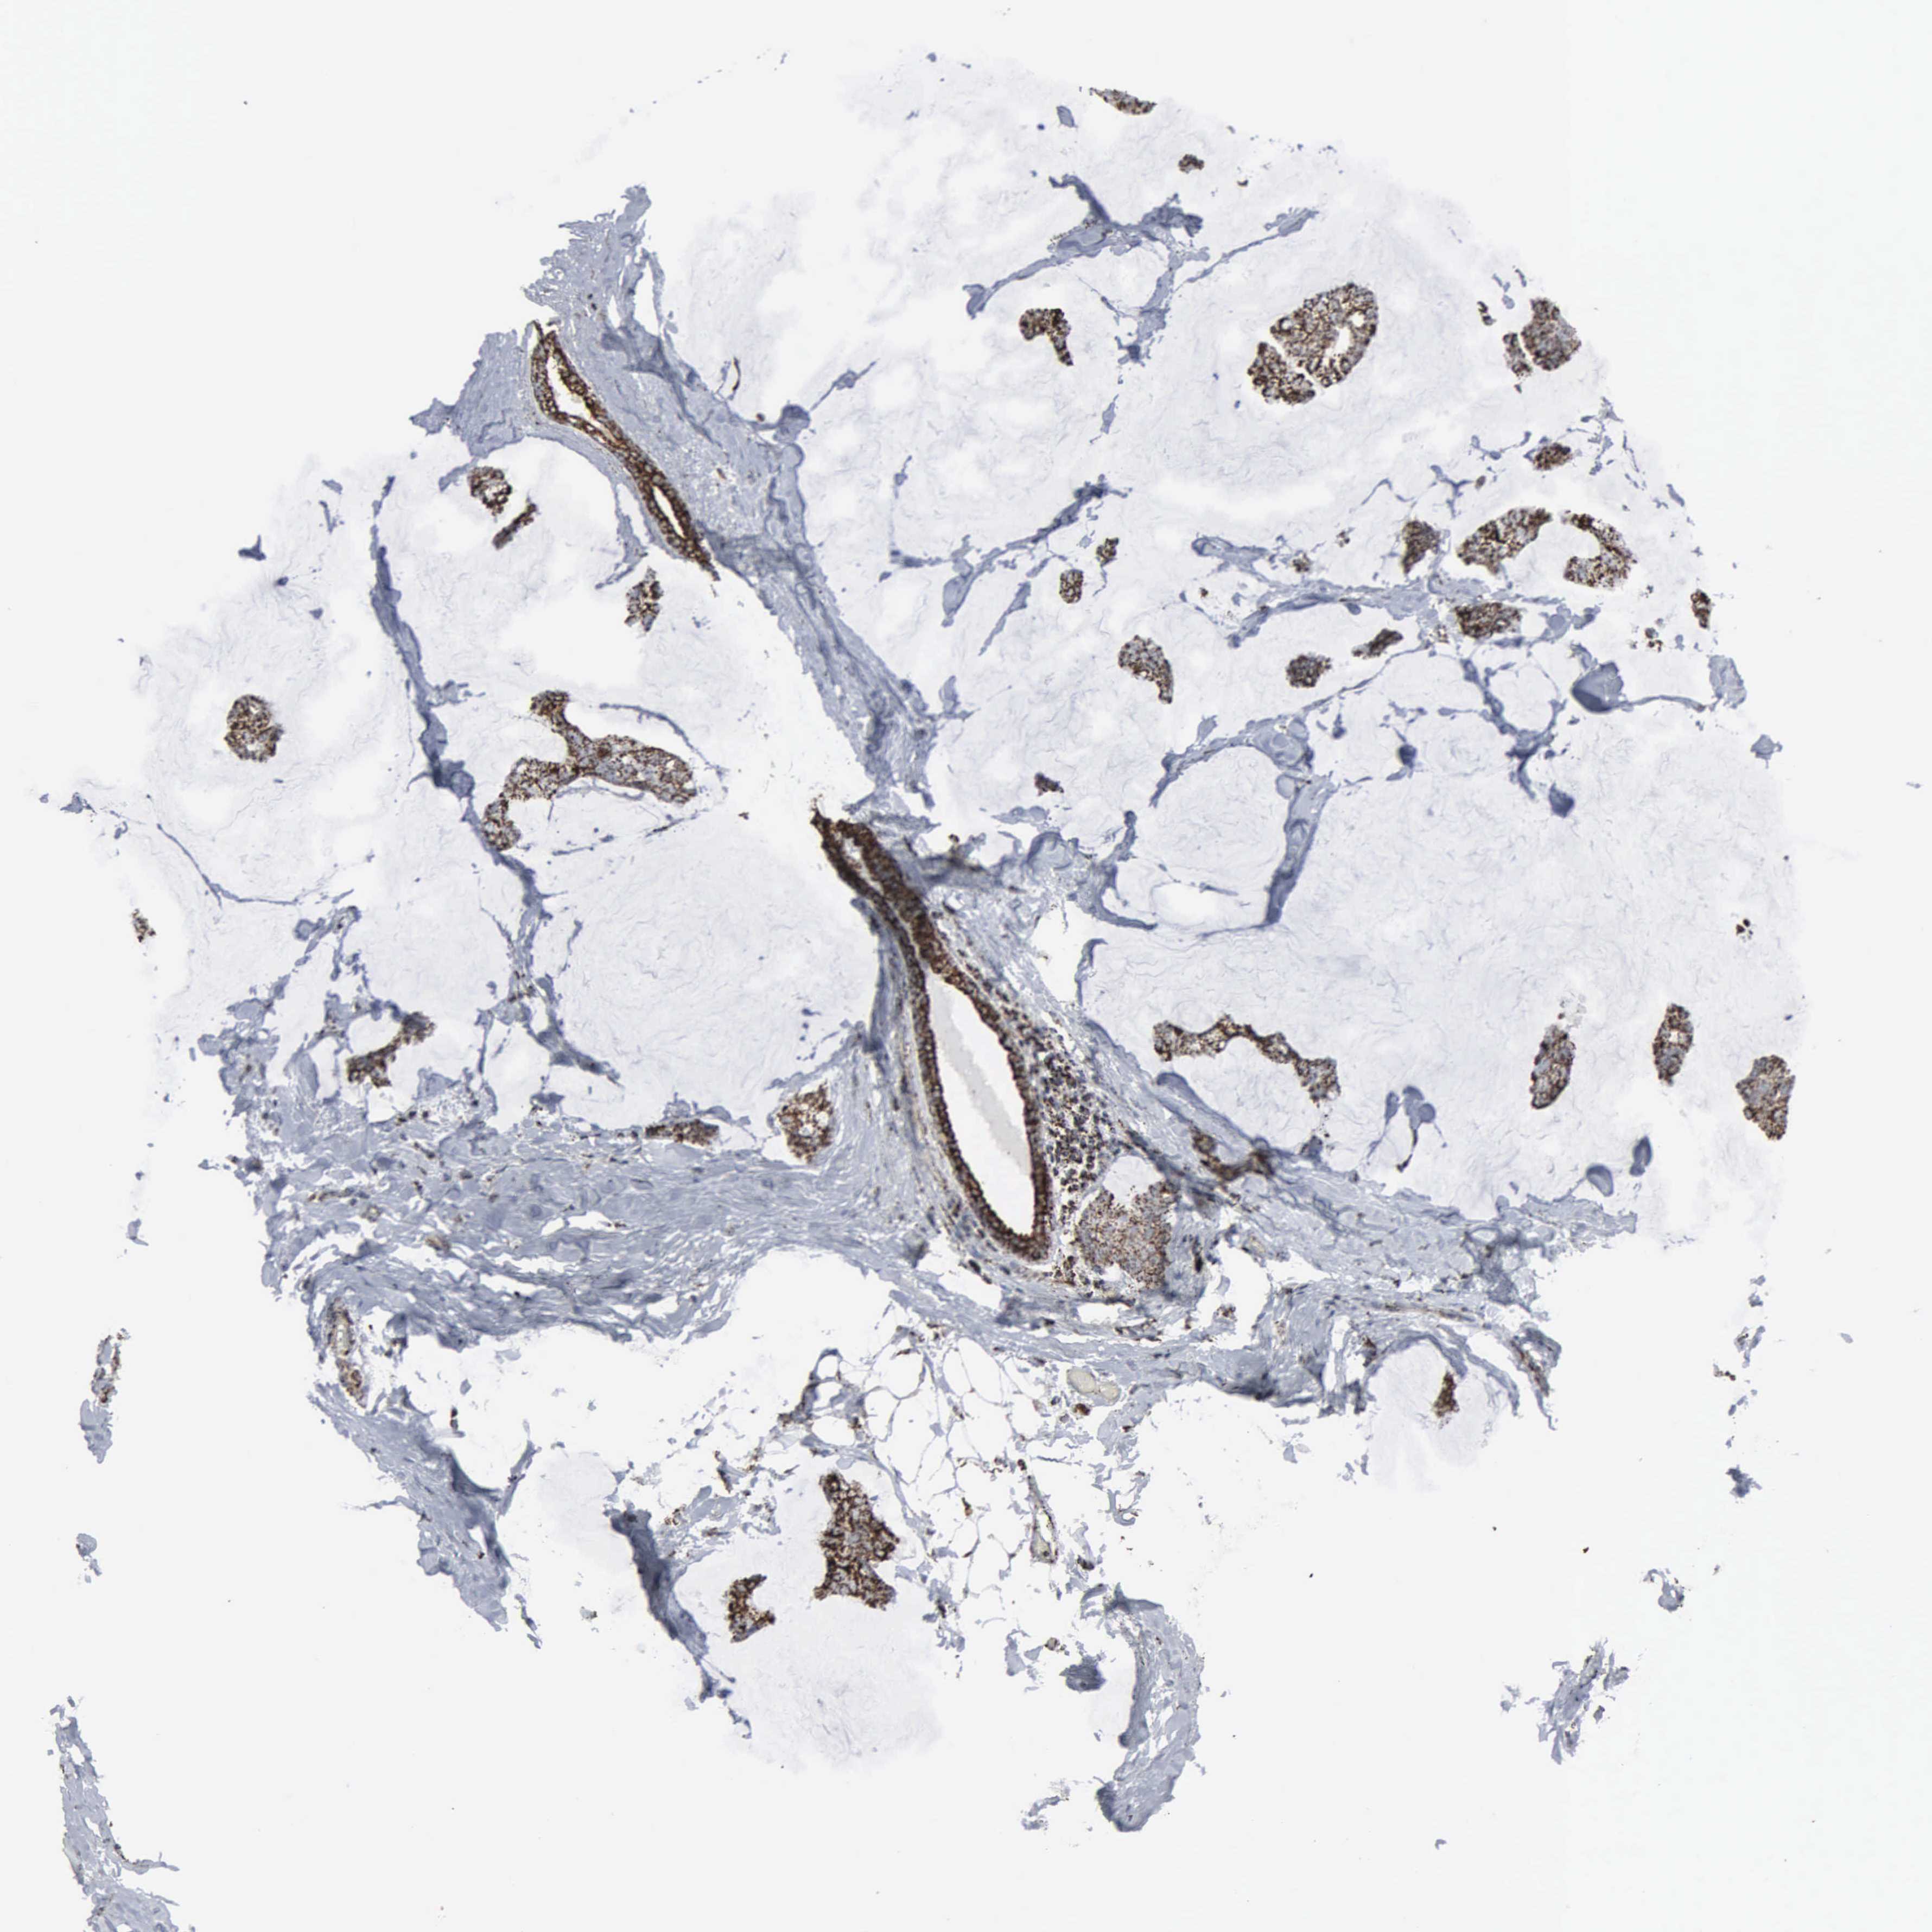

CANCER BREAST CANCER Show tissue menu

BRCA TCGA BRCA VALIDATION PROTEIN EXPRESSION